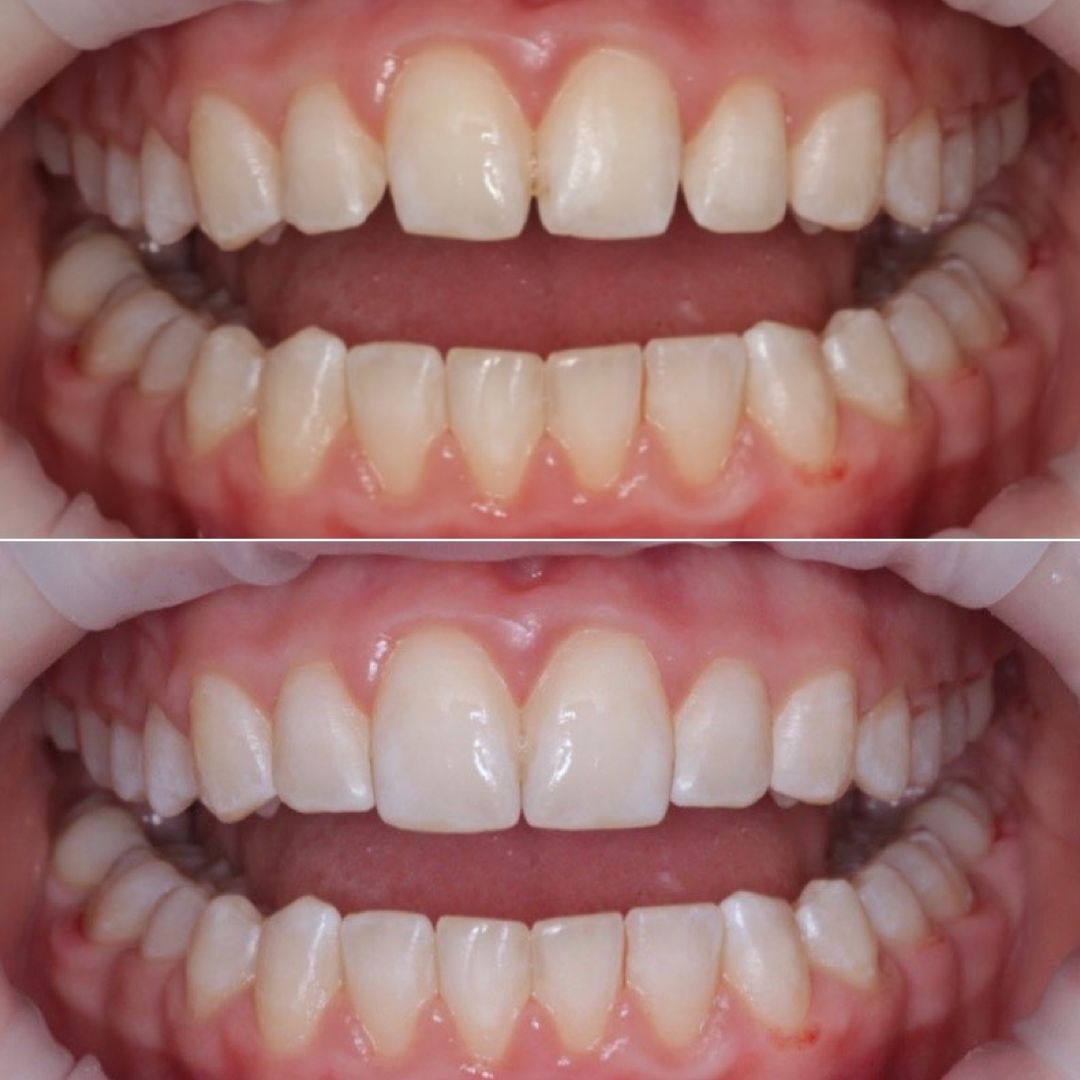

Jej pasją jest leczenie zachowawcze, wypełnienia z jej ręki są małymi dziełami sztuki, idealnie i anatomicznie wykończonymi. Precyzja i cierpliwość w sposobie pracy w połączeniu z wysokim poczuciem estetyki umożliwiły tej naturalny rozwój w kierunku stomatologii estetycznej. Dr Valeriia wykonuje precyzyjne kompozytowe odbudowy zębów przednich, bondingi oraz prace „z ręki”.

Doktor uważa, że obraz mówi więcej niż słowa, zapraszamy do zapoznania się z galerią jej prac.